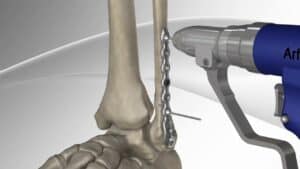

Prelom kostiju operacija

U slučajevima kada je potrebna operacija preloma zahvaljujući savremenom pristupu brojne prelome rešavamo minimalno invazivno, praktično sa minimalnim ili bez dodatnih značajnih oštećenja tkiva tokom intervencija sa očekivano brzim oporavkom.

Brojne intervencije, i operacije preloma, izvedene na savremen način modernim implantima karakteriše vrlo kratko zadržavanje i ubrzan oporavak.